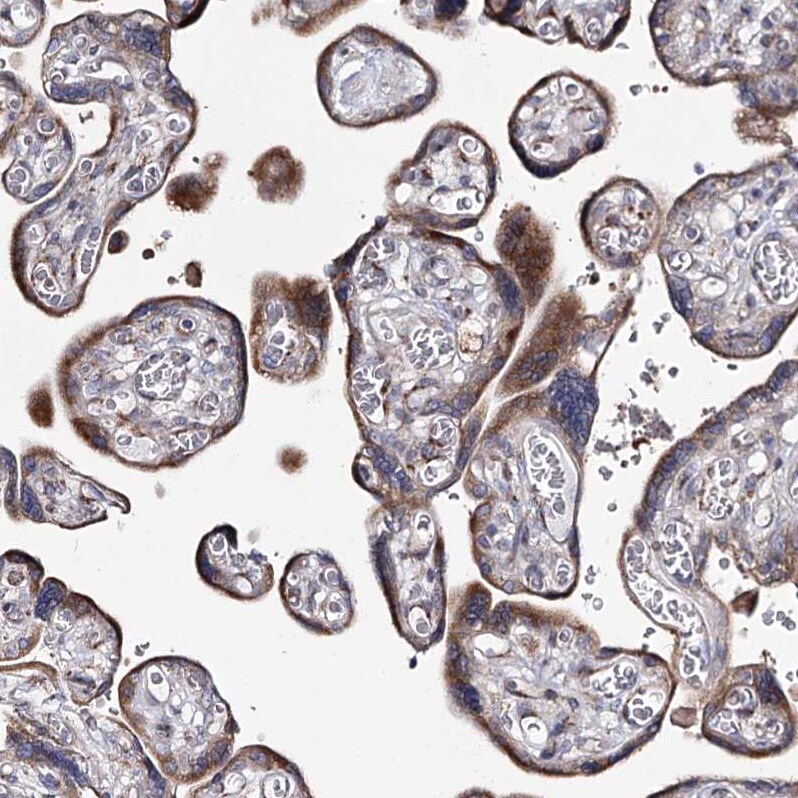

- Immunohistochemical analysis of C5orf42 in human placenta using C5orf42 Polyclonal Antibody (Product # PA5-57810) shows moderate granular cytoplasmic positivity in trophoblastic cells.